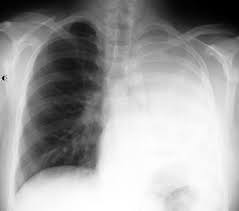

Mucus a slippery and sticky fluid found throughout the body plays an important role in the health of the respiratory system. If the mucous plug is in one of the smaller bronchial tubes the air behind the plug and the smallest airways called alveoli gets absorbed and this condition is called atelectasis. Mucus also acts as a trap for irritants like dust smoke or bacteria. Mucus plugs in the lungs generally develop in response to chronic underlying conditions of the respiratory or nervous system that weaken the lungs or surrounding muscles.

A lung mucus plug occurs when too much of the naturally occurring mucus is present without being cleared away through the normal processes. A term patient gradually loosing the mucus plug is indicating progression towards labor. What is mucus plug in the lungs. The mucous membrane lining also helps in maintaining moistness of the respiratory tract.